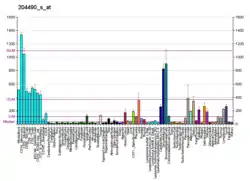

CD44 is expressed in a large number of mammalian cell types. The standard isoform, designated CD44s, comprising exons 1–5 and 16–20 is expressed in most cell types. CD44 splice variants containing variable exons are designated CD44v. Some epithelial cells also express a larger isoform (CD44E), which includes exons v8–10.[6]

CD44 participates in a wide variety of cellular functions including lymphocyte activation, recirculation and homing, hematopoiesis, and tumor metastasis.

Transcripts for this gene undergo complex alternative splicing that results in many functionally distinct isoforms; however, the full length nature of some of these variants has not been determined. Alternative splicing is the basis for the structural and functional diversity of this protein, and may be related to tumor metastasis. Splice variants of CD44 on colon cancer cells display sialofucosylated HCELL glycoforms that serve as P-, L-, and E-selectin ligands and fibrin, but not fibrinogen, receptors under hemodynamic flow conditions pertinent to the process of cancer metastasis.[11][12]